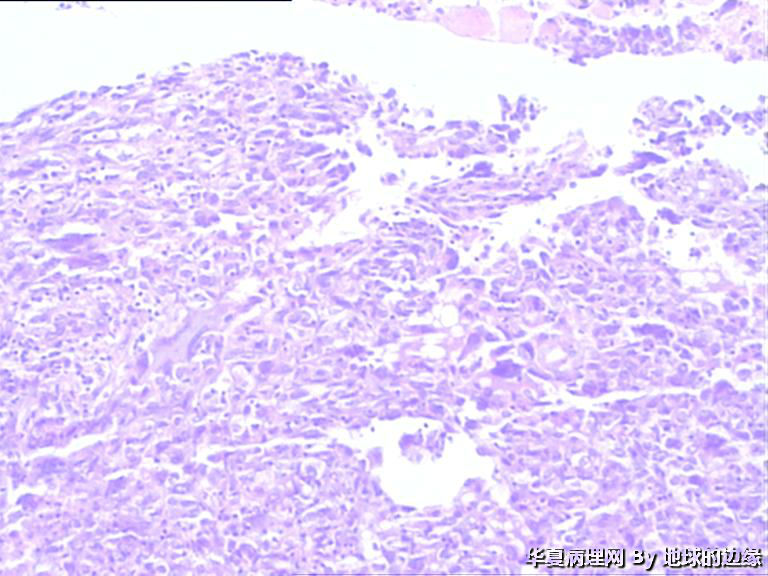

病人女性,48岁

MRI示:右肱骨肿瘤待排,包块大小为10x8cm,活动度差,边界欠清,鱼肉组织(白色),肿块侵犯至骨外    组  织。

• 右肱骨肿瘤待查图2

图2

恶性。是转移还是原发,是骨肉瘤还是浆母?需要进一步资料并标记。

考虑肉瘤,转移癌也排除一下吧